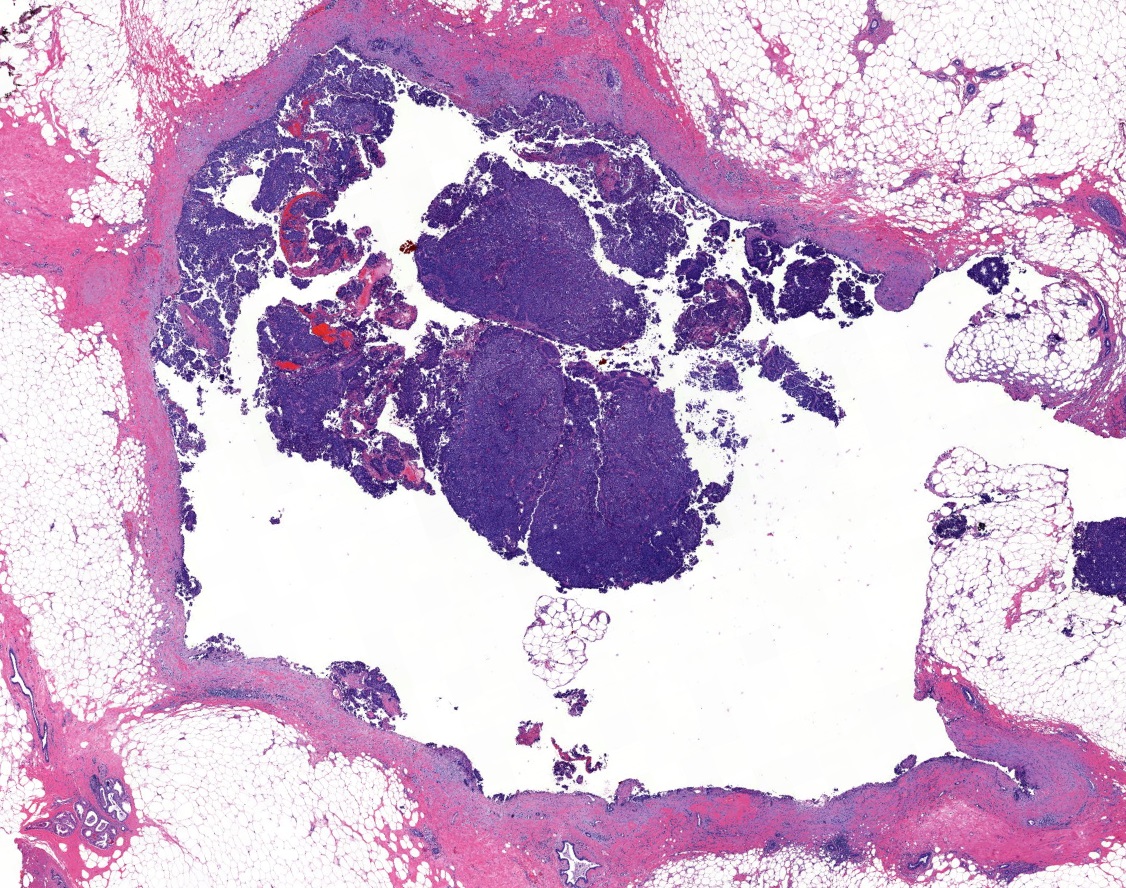

- Papillary tumor with pushing borders, may be within a cystically dilated duct, surrounded by a thick fibrous capsule (Histopathology 2008;52:20, Mod Pathol 2021;34:1044, Virchows Arch 2022;480:5)

- Delicate papillary fronds with fibrovascular cores lined by cuboidal to columnar epithelial cells with low to intermediate grade atypia

- Cribriform and solid architecture may be present

- Most show complete lack of myoepithelial cells along the papillae and around the periphery of the tumor (Am J Surg Pathol 2006;30:1002, Am J Surg Pathol 2011;35:1)

- Invasive carcinoma is defined as the presence of neoplastic cells infiltrating beyond fibrous capsule (Mod Pathol 2021;34:1044)

- Epithelial displacement / entrapment of neoplastic cells within capsule can occur and must be distinguished from true invasion beyond the fibrous capsule

Microscopic (histologic) images

Contributed by Kristen E. Muller, D.O. , Mariel Molina Nunez, M.D. and Julie Jorns, M.D. (Case #518)